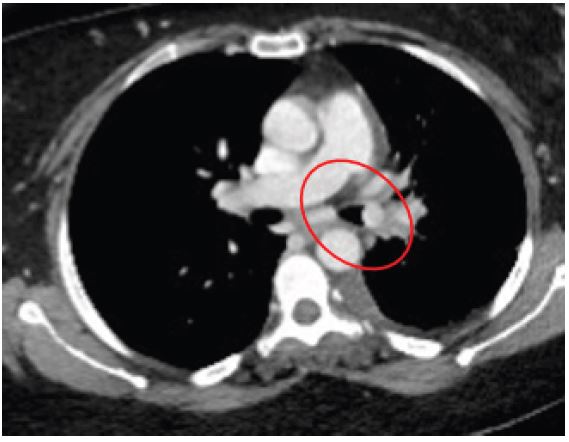

A 42-year-old male presented to our outpatient clinic with a 2-month history of persistent dry cough, mild exertional dyspnea, and occasional wheezing. He was a non-smoker with past history of Bronchial Asthma which was diagnosed 3 years back and patient was on Inhaled salbutamol on as needed basis. Clinical auscultation revealed a localized wheeze over the right lower lobe. Chest X-ray showed a suspicious opacity. CT chest revealed a well-defined lesion at the origin of the right lower lobe bronchus. Bronchoscopy visualized an endobronchial mass, and biopsy confirmed a typical carcinoid tumor.

Figure 1: Chest X-ray showing an opacity in the right lower lobe.